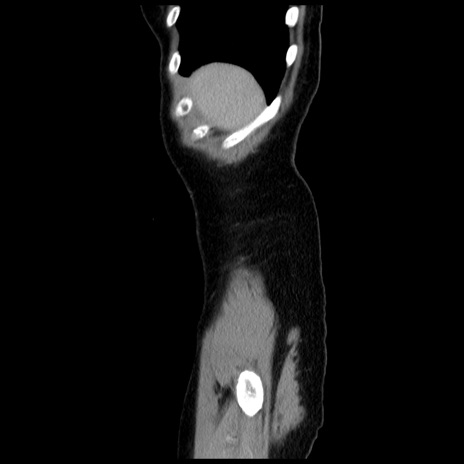

症例10(矢状断像)

【症例】 50歳代女性

【主訴】 腹痛

【現病歴】前日生レバーを食べた。今朝に排便あり。 昼前に突然発症の腹痛を生じ、当院救急外来を受診した。

【既往歴】 子宮筋腫にてで子宮全摘後

【身体所見】 意識清明、腹部:平坦、軟、下腹部やや左を中心に圧痛・反跳痛あり、筋性防御あり

【データ】WBC 7800、CRP 0.07